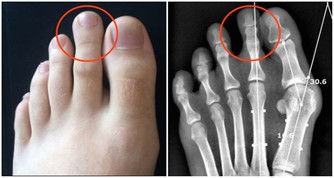

5、缺鈣

鈣離子在肌肉收縮過程中起著重要作用。當血液中鈣離子濃度太低時,肌肉容易興奮而痙攣。青少年生長發育迅速,很容易缺鈣,因此就常發生腿部抽筋。